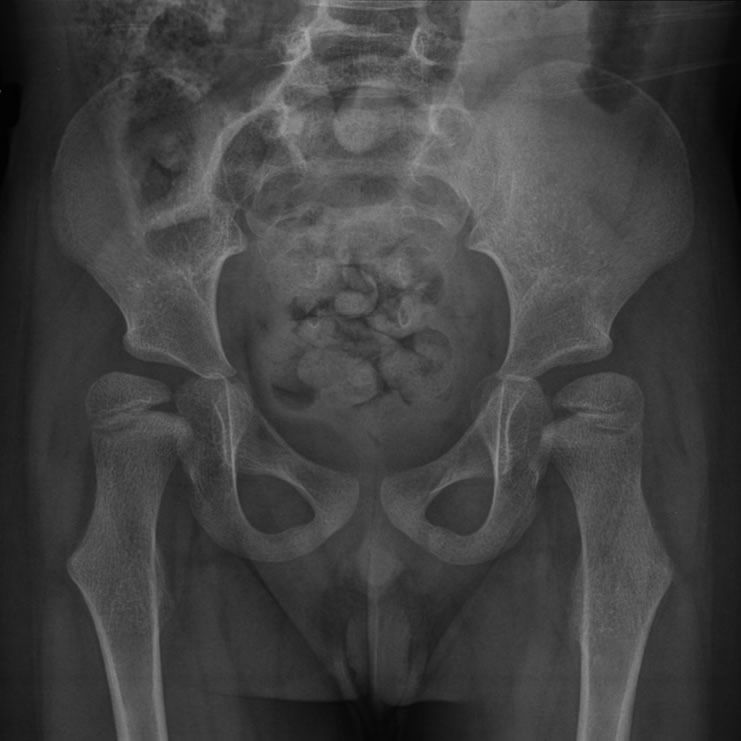

O acompanhamento do quadril é essencial na Paralisia Cerebral, especialmente nos níveis GMFCS IV e V, devido ao alto risco de luxação causado por desequilíbrio muscular e alterações ósseas.

Quando não tratada, a luxação pode provocar dor, dificultar a higiene e o posicionamento e prejudicar a qualidade de vida. Por isso, a vigilância ortopédica regular é fundamental.